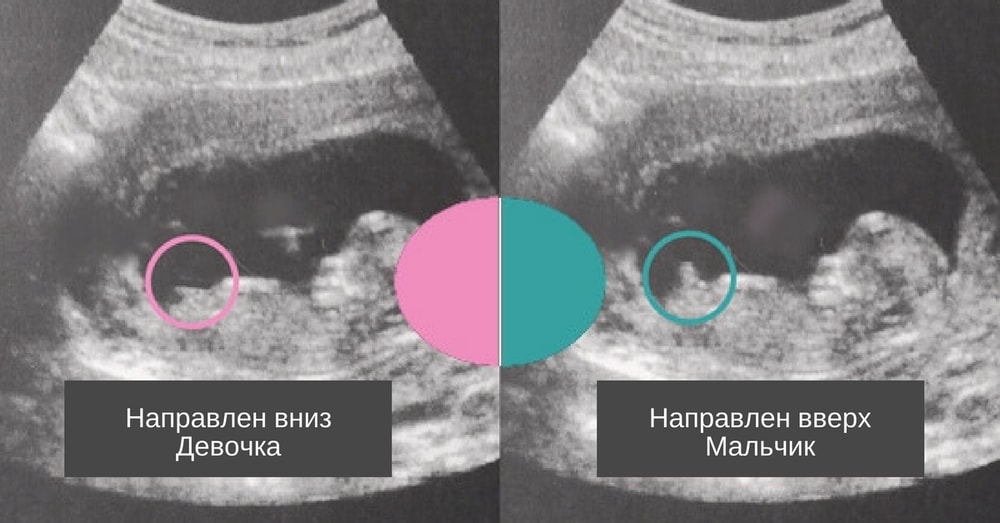

К сожалению нет объективного кадра , где хорошо было бы видно бугорок … между ножек смотреть нет смысла , на этом сроке писюлька у всех торчит одинаково , девочки еще девочками не стали … а так у меня 3 беременность , всегда давали 70% на 1 скрининге и всегда это совпадало ) поэтому готовьтесь к мальчику по большей степени 💙

Половой бугорок не на девочку скорее вообще, а между ножек не показательно вообще, оно одинаково у всех.